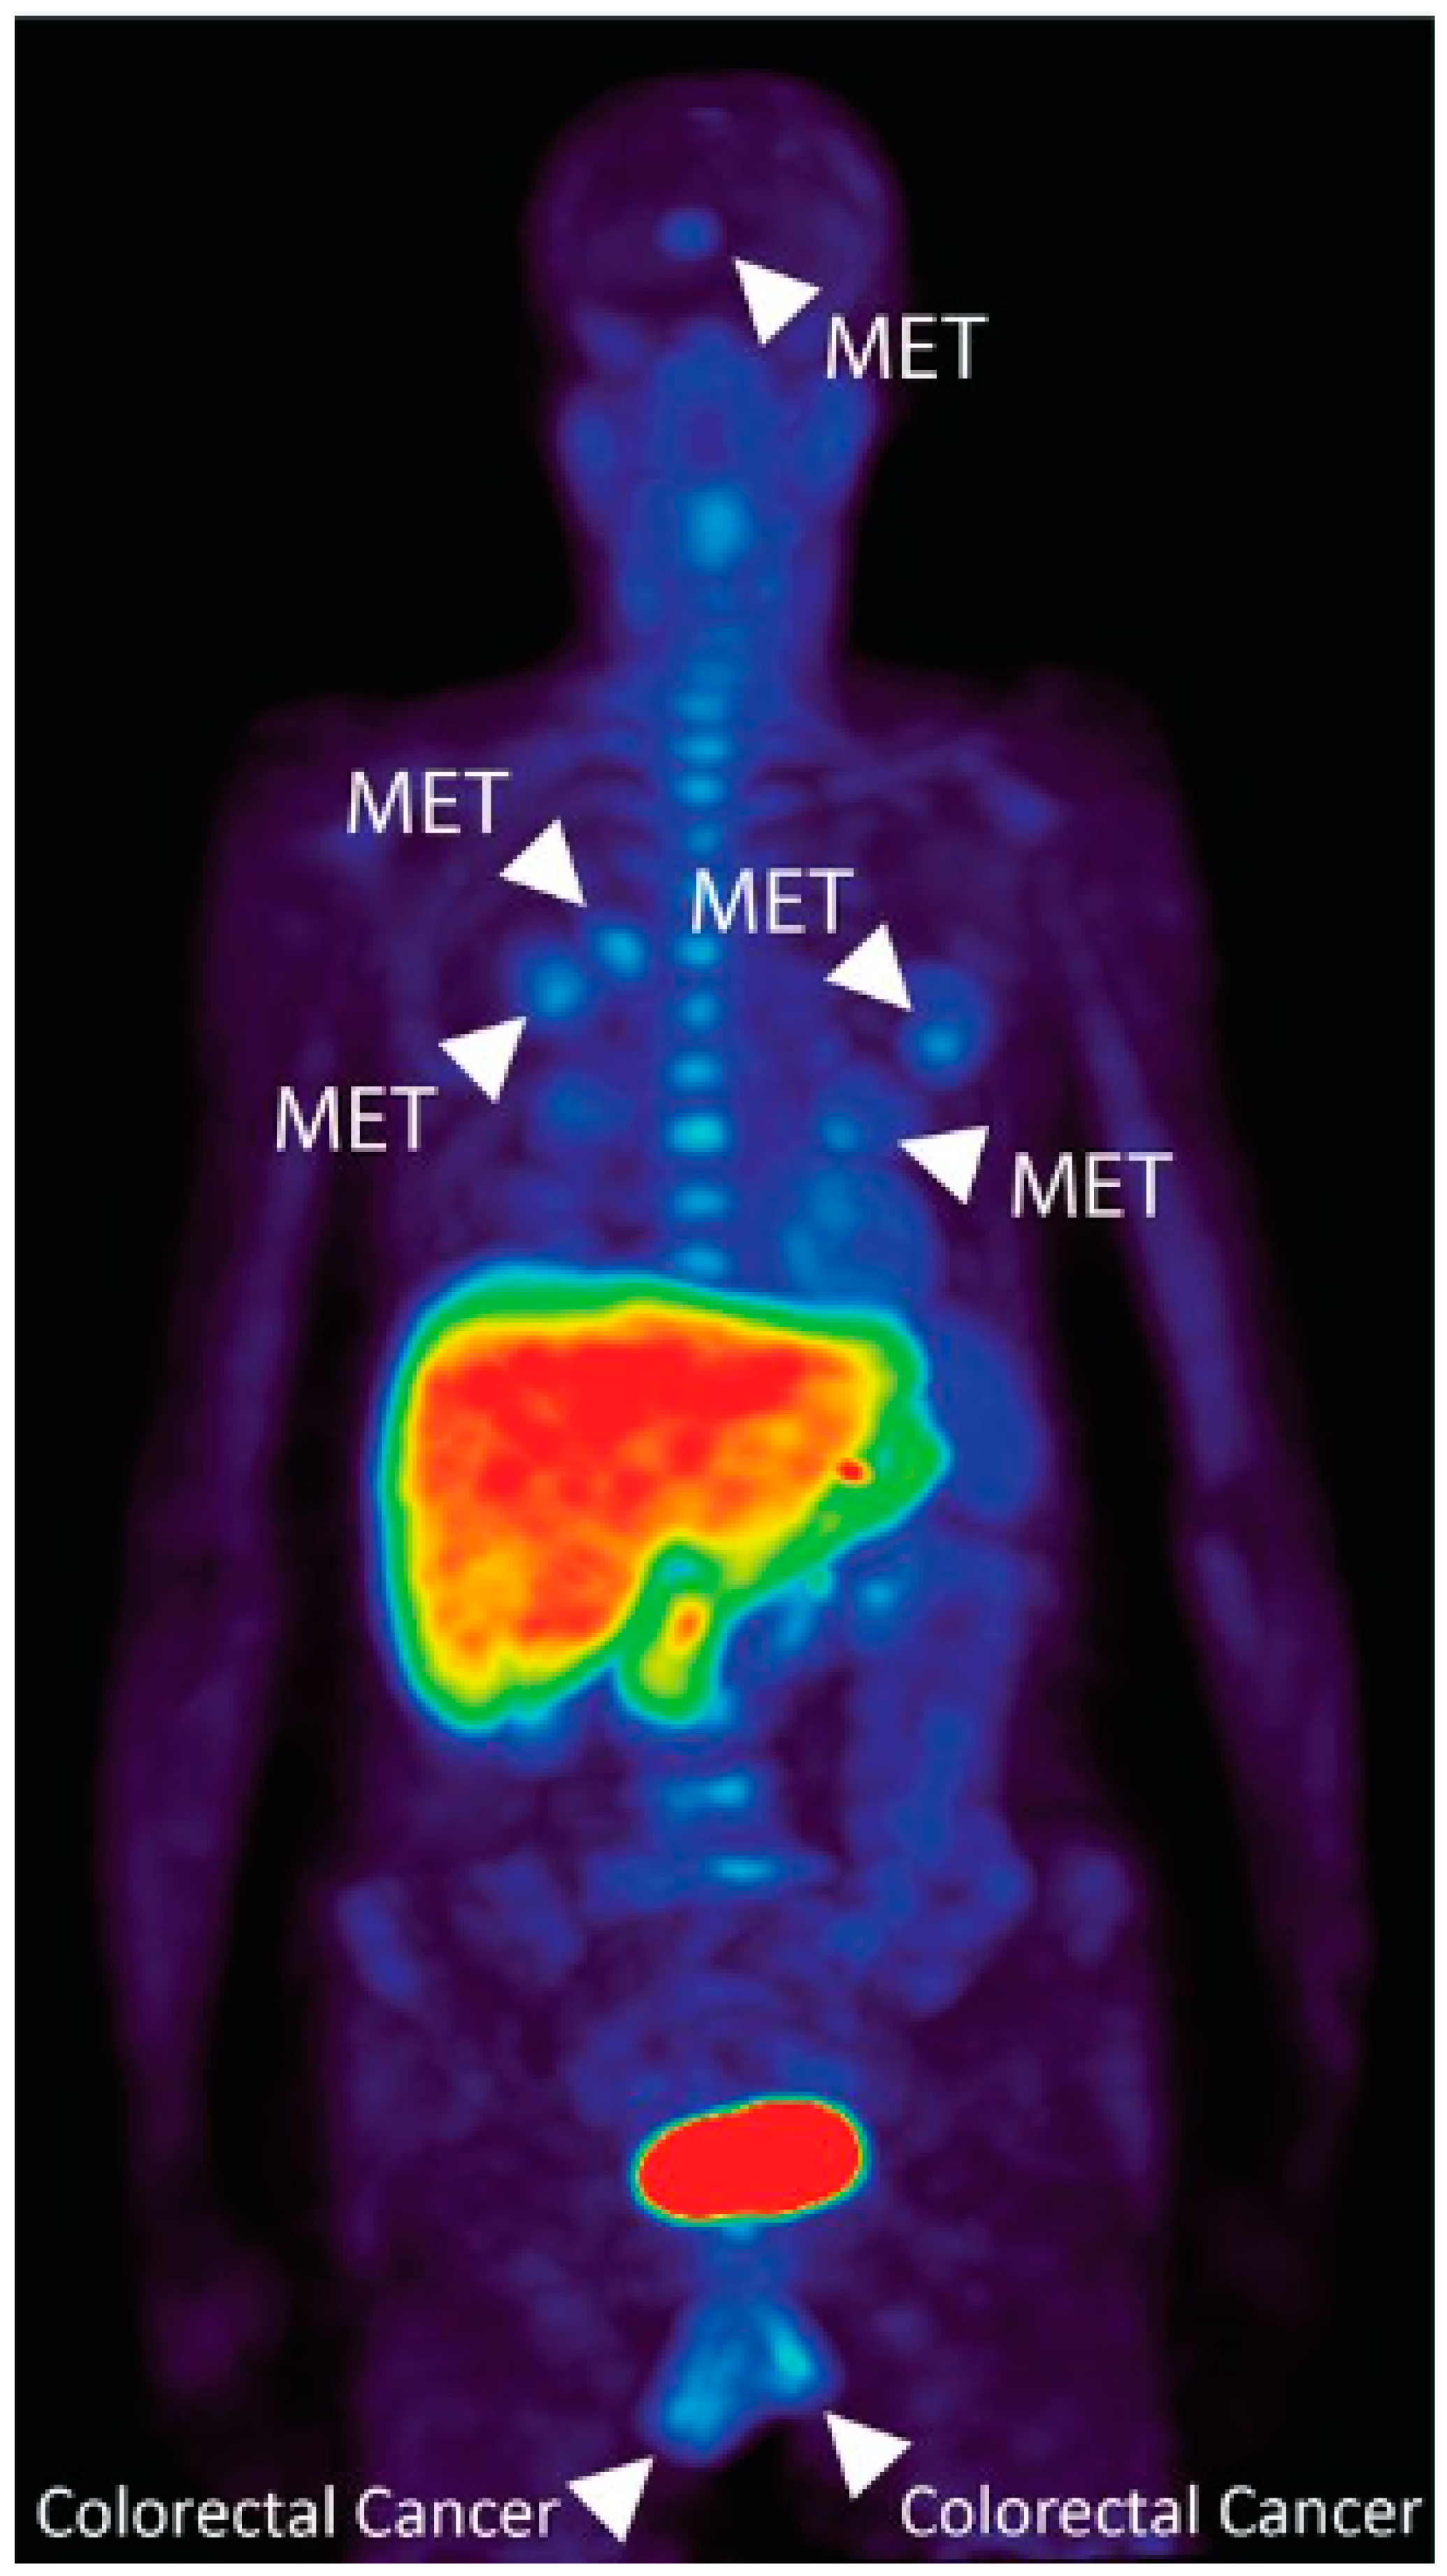

- Kratochwil, C.; Flechsig, P.; Lindner, T.; Abderrahim, L.; Altmann, A.; Mier, W.; Adeberg, S.; Rathke, H.; Röhrich, M.; Winter, H.; et al. 68Ga-FAPI PET/CT: Tracer Uptake in 28 Different Kinds of Cancer. J. Nucl. Med. Off. Publ. Soc. Nucl. Med. 2019, 60, 801–805. [Google Scholar] [CrossRef] [PubMed]